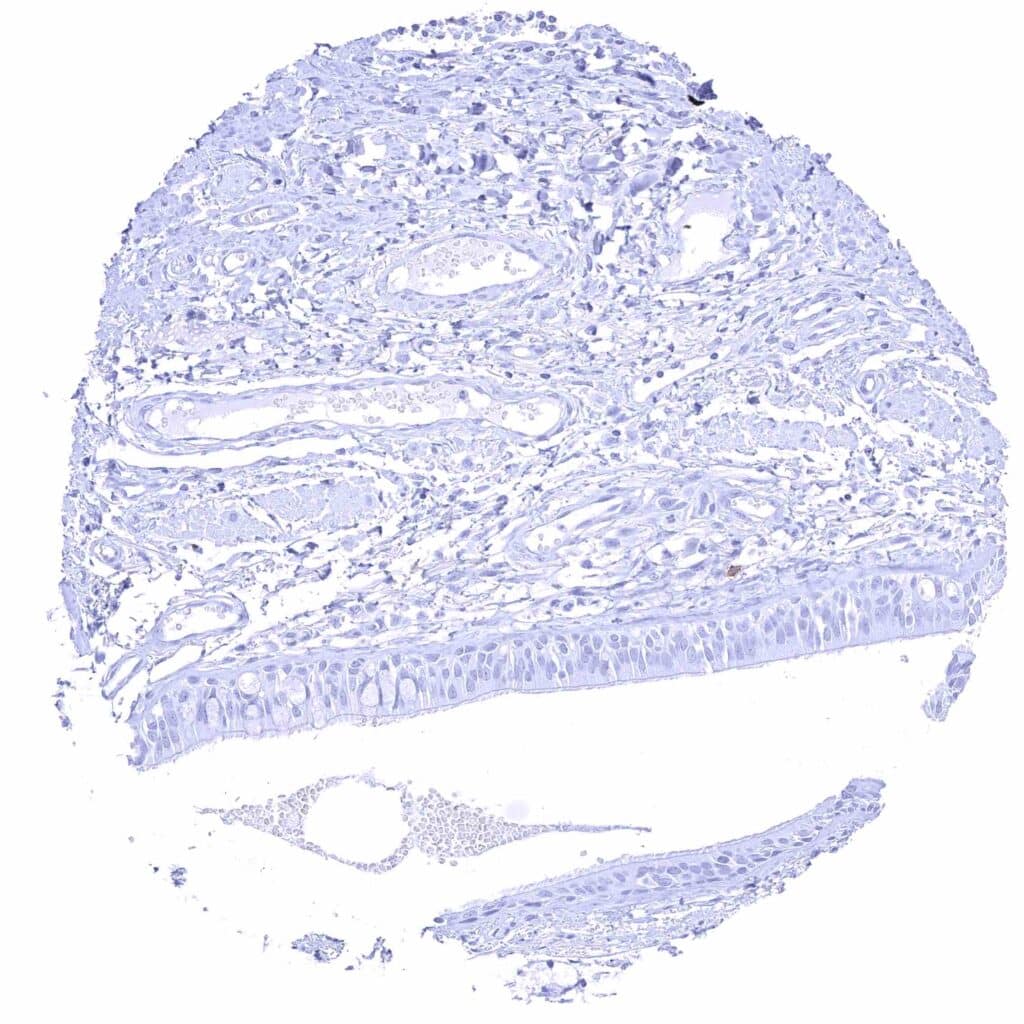

Uterus, ectocervix